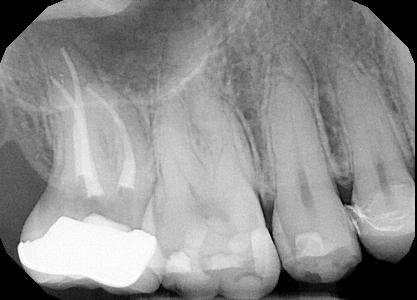

Treatment of tooth #5 ( upper right bicuspid) with an extra canal!